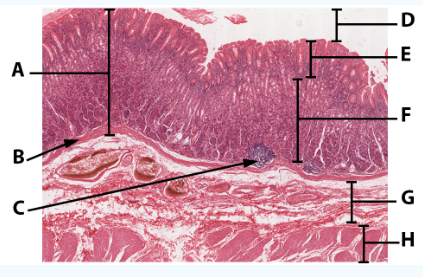

A

Mucosa

B

Muscularis mucosa

C

MALT

D

Lumen

E

Gastric pits: simple columnar epithelium

F

Gastric glands

G

Submucosa

H

Muscularis externa: oblique, circular, and longitudinal

area

Stomach